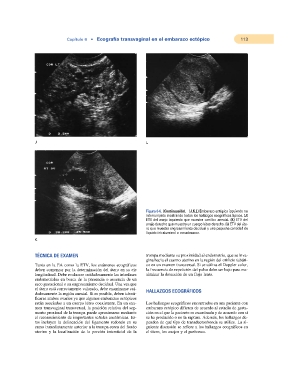

Figura 6-6. (Continuación). (J,K,L) Embarazo ectópico izquierdo no

interrumpido mostrando todos los hallazgos ecográficos típicos. (J)

ETV del anejo izquierdo que muestra «anillo» anexial. (K) ETV del

anejo derecho que muestra un cuerpo lúteo derecho. (L) ETV del úte-

ro que muestra engrosamiento decidual y una pequeña cantidad de

líquido intraluminal o «seudosaco».